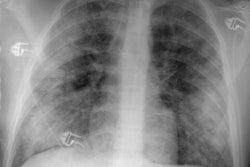

Sarcoid Stage 1:

The patient is an active duty troop who presented to the emergency department because of URI complaints. The chest radiograph demonstrated right paratracheal and bilateral hilar adenopathy (the "1-2-3 sign" of sarcoid). Transbronchial biopsy confirmed the diagnosis of sarcoid. (Click here to view the lateral exam which demonstrated increased density over the hila)